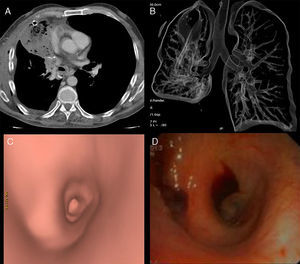

Presentamos el caso de un paciente de 56 años con un nódulo en LSD de características malignas. Tras resección mediante lobectomía superior derecha, presenta hemoptisis franca y taquicardia, con opacidad pulmonar persistente en las radiografías. Se realiza TCMD de tórax con contraste iv, que muestra consolidación expansiva del lóbulo medio con ausencia de realce, distorsión bronquial perihiliar y alteración de relación normal de vasos pulmonares. La broncoscopia virtual muestra obliteración de la luz de bronquio lobar medio. La broncoscopia óptica revela la comprensión en «boca de pez» del bronquio, que impide el paso del fibrobroncoscopio. Se sospecha torsión e infarto del lóbulo medio, y se realiza lobectomía media urgente que confirma el diagnóstico.